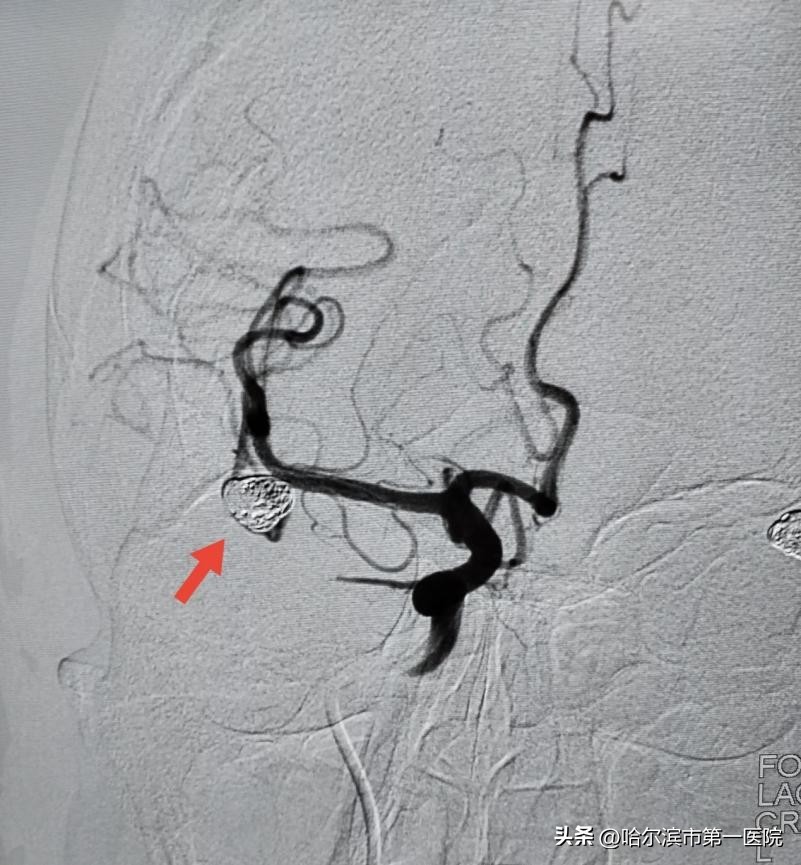

前不久,闫女士在抬东西时,用力后突然出现剧烈头痛,症状持续不缓解,紧急到医院查头部CT发现是蛛网膜下腔出血,急诊来到哈尔滨市第一医院进行救治。医院急诊为其行全脑血管造影,结合既往病史和CT表现,提示下腔出血集中在右侧侧裂,考虑为右侧大脑中动脉分叉动脉瘤破裂造成,市一院专家们迅速制定手术方案,行动脉瘤弹簧圈栓塞术,术后患者经过9天精心治疗和护理,目前已出院。